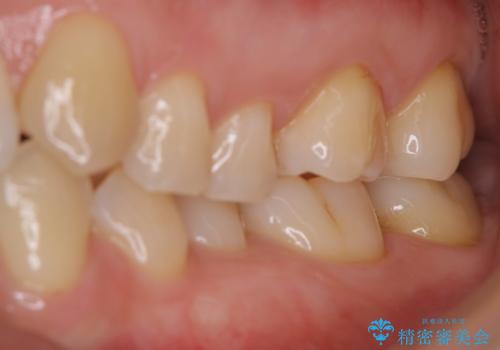

- 毎日歯磨きをしているのに、奥歯のザラつきが気になるとのことでした。プラーク・歯石・ステインが付着していたためPMTC60分コースを行いました。

また、汚れを除去することでご自身本来の歯の表面となり、歯磨きだけでは得られないツルツル感と、全体的に明るい印象に仕上がります。